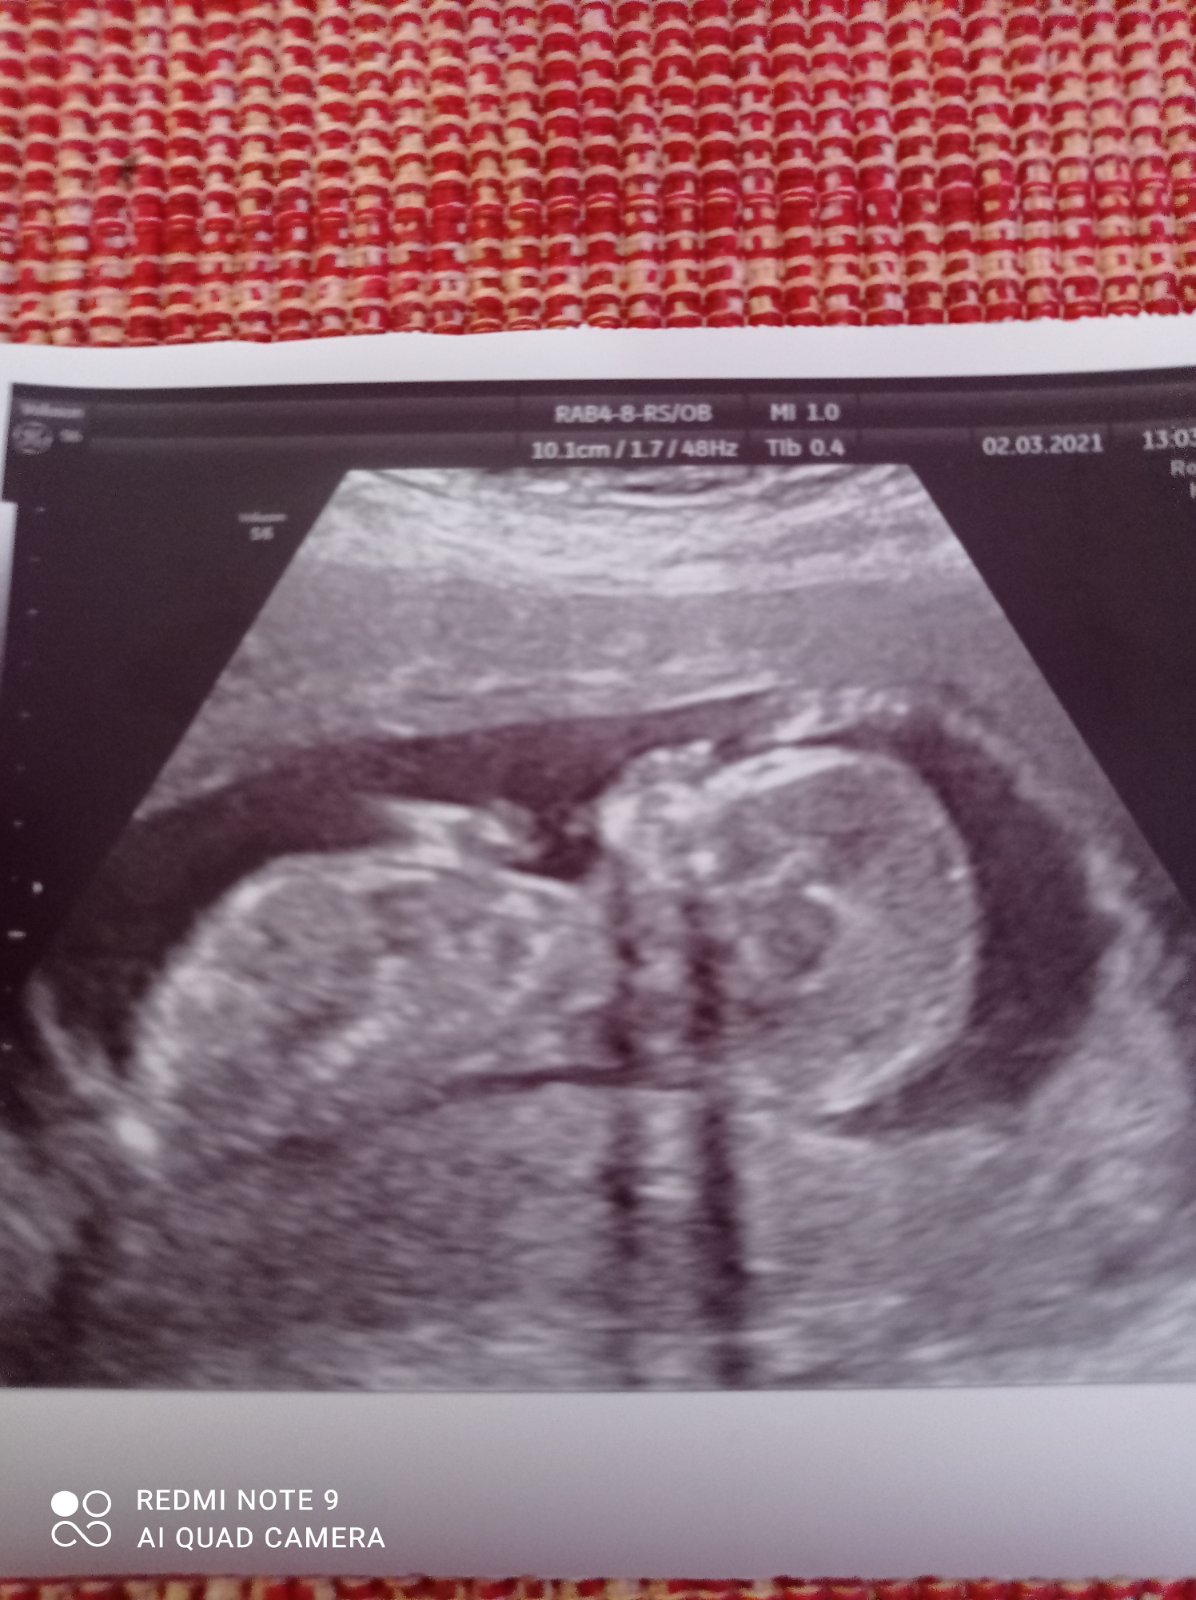

Bude to chlapček či dievčatko?

boze zeny cinsky horoskop mi povedal, ze dievca cakame chlapca, tvar brucha mam, ze dievca cakame chlapca, som cela vyhadzana aka dievca mi berie krasu, cakame chlapca a mame ho jasne potvrdeneho ultrazvukom v 20tt

@petamich rovnako podla vsetkeho cakam dievca (az na sodu, lebo to by ma ani nenapadlo skusat) a aj hla, moja dcerenka ma vajcia 😂

@babovka2321 veru sodu som ani ja neskusala 🙂 to ja len som od okolia pocuvala tieto babske povery a podla nich boli vsetci presvedceni, ze to bude dievca no ale aj ta nasa ma jasneho pipika 🙈🙈